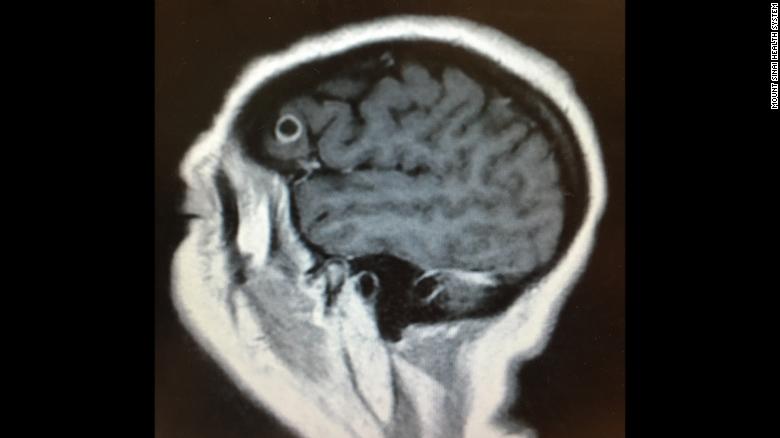

În timpul acestei lupte, severitatea simptomelor vizuale i-a determinat pe medici să facă un RMN, unde au găsit ceea ce se credea că este o tumoare care provoacă durerea. La îndepărtarea leziunii, au descoperit că masa nu era o tumoare, ci mai degrabă un chist plin de larve de tenie!